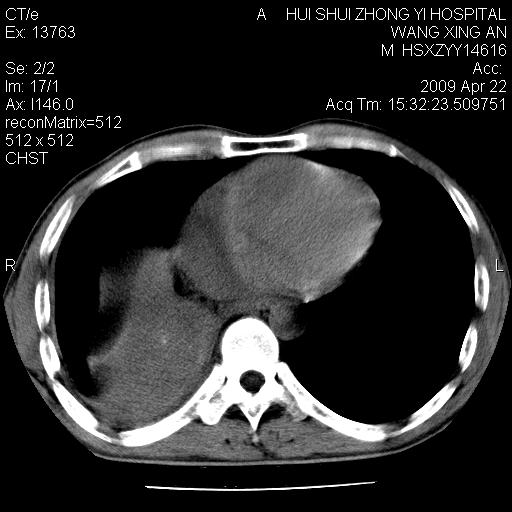

标题: CT19534:患者男、46岁咳嗽、胸痛半月。 [打印本页]

标题: CT19534:患者男、46岁咳嗽、胸痛半月。

1、右下肺中央型肺癌并右肺转移,右肺下叶不张。(肿块围绕右肺下叶支气管生长,致管腔闭塞右肺下叶不张;右肺有结节影)。

2、右侧胸腔积液。

3、右中上肺陈旧性肺结核(右肺见纤维化病灶及点状钙化)。